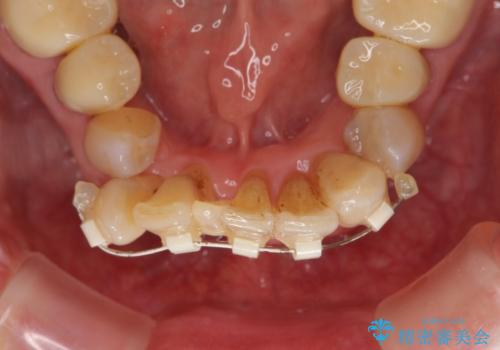

銀歯を高強度の仮歯に替えたのち、下顎前歯のみの部分矯正→全体的なマウスピース矯正治療(インビザライン)→最終的なセラミック治療と治療を進めます。

矯正治療と目立つ銀歯のやりかえを行ったことでかみあわせだけでなく、審美性・清掃性も改善し口腔内の環境を劇的に改善することができました。